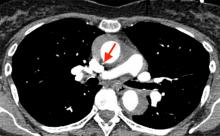

Figure 1: Computed tomography angiography scan

At the time of surgery, transesophageal echocardiogram (TEE) confirmed significant intramural hematoma in the ascending aorta, as well a raised suspicion for aortic rupture (Fig. 1). Upon opening the pericardium, the ascending aortic pathology was obvious with the typical discolored appearance. Cardiopulmonary bypass was established via the left femoral artery and right atrium.